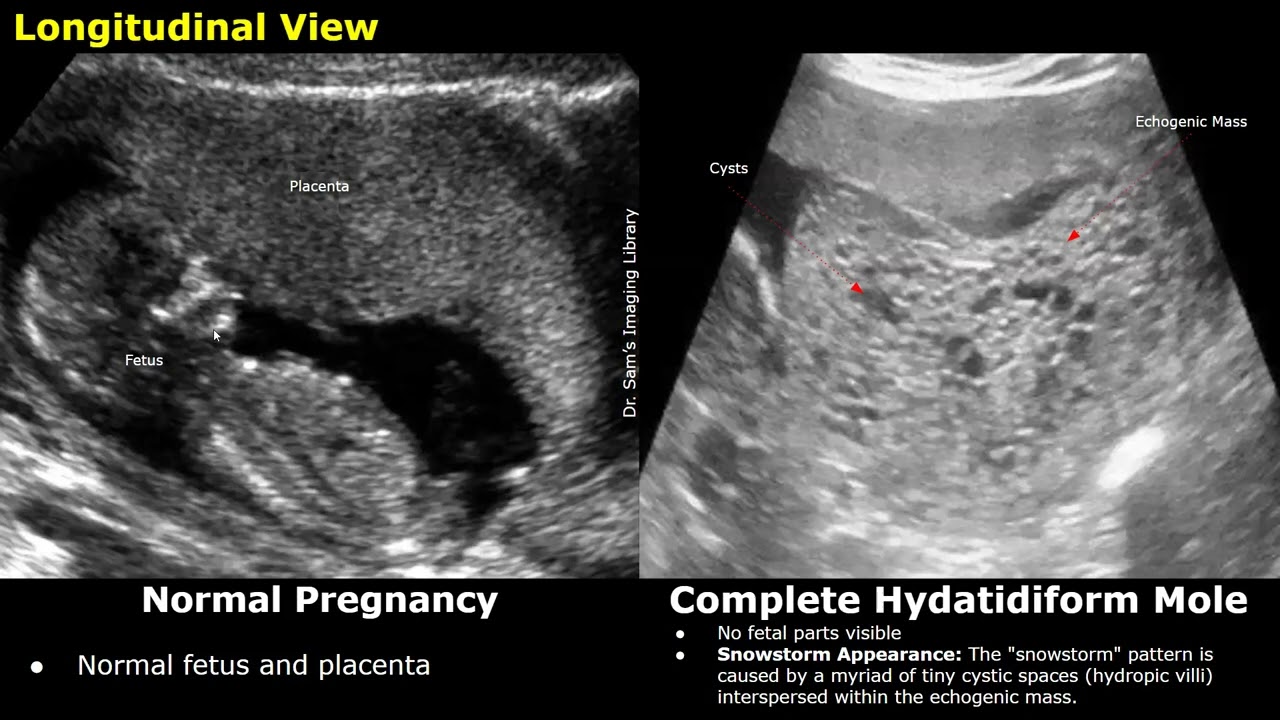

Obstetric Ultrasound Normal Vs Complete Hydatidiform Mole Images | Molar Pregnancy USG Cases

Gestational Trophoblastic Disease: Complete Hydatidiform Mole

Ultrasound findings are often supported by extremely high beta-hCG levels (disproportionate to the gestational age) and clinical features such as vaginal bleeding, hyperemesis gravidarum, or symptoms of hyperthyroidism.

No fetal parts visible

Snowstorm Appearance: The "snowstorm" pattern is caused by a myriad of tiny cystic spaces (hydropic villi) interspersed within the echogenic mass.

Enlarged uterus

Areas of increased vascularity